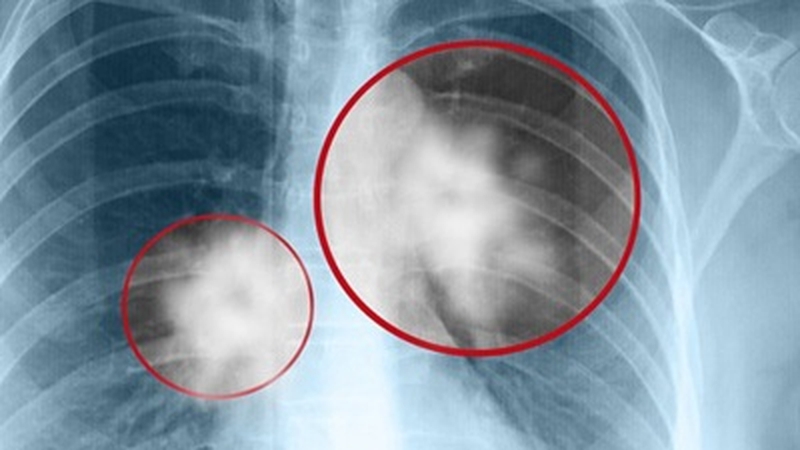

Ung thư phổi di căn xương có triệu chứng gì? Sống được bao lâu?

Ung thư phổi di căn xương gây cảm giác đau đớn và khó chịu, đây là giai đoạn tế bào đột biến từ phổi lây lan đến khu vực xương.

Ung thư phổi di căn xương gây cảm giác đau đớn và khó chịu, đây là giai đoạn tế bào đột biến từ phổi lây lan đến khu vực xương. Nó có thể thông qua đường máu hoặc hệ bạch huyết. Loại ung thư này làm tăng nguy cơ gãy xương, làm cản trở các hoạt động và chất lượng cuộc sống bị giảm. Bệnh ung thư này rất phổ biến ở những người bị ung thư đang trong giai đoạn cuối. Nó làm ảnh hưởng lên tới 30 – 40% những người đang trong giai đoạn 3 hoặc 4.